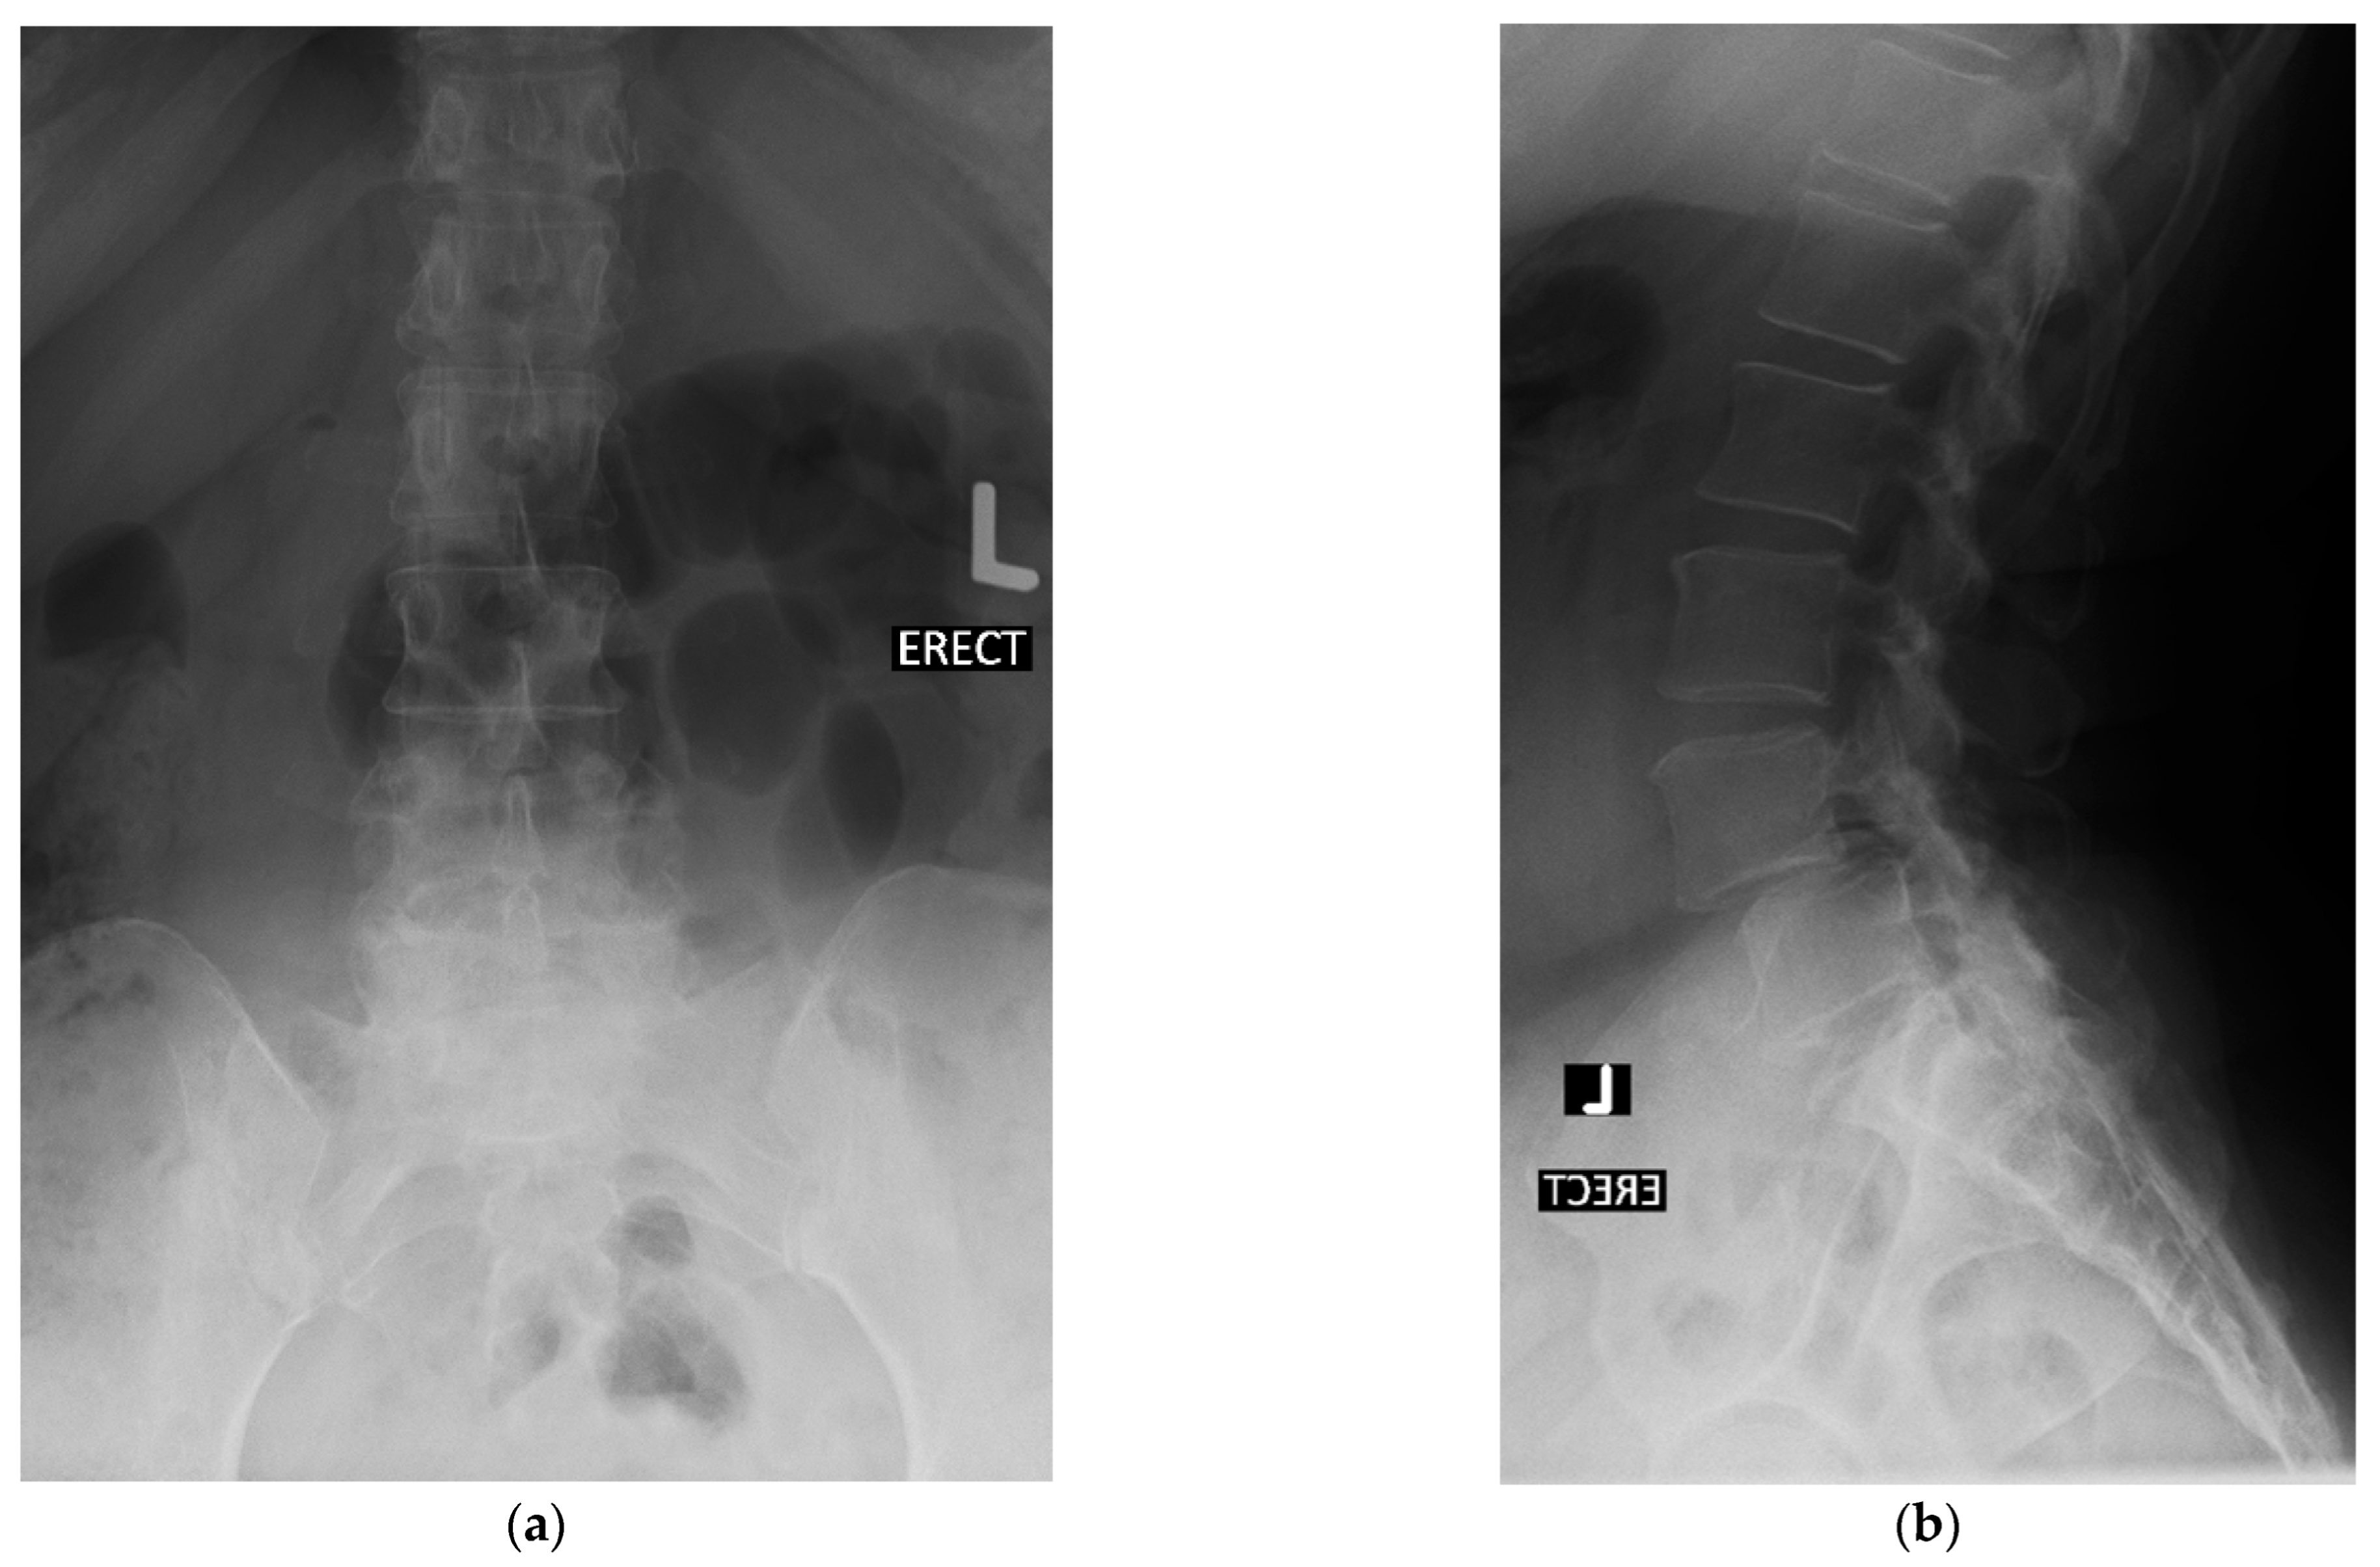

4.1. Case 1: Madam M

4.2. Case 2: Madam R

4.3. Case 3: Madam M